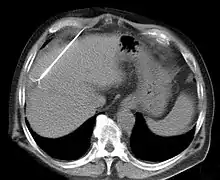

RFA may be performed to treat tumors in the lung,[6][7][8] liver,[9] kidney, and bone, as well as other body organs less commonly. Once the diagnosis of tumor is confirmed, a needle-like RFA probe is placed inside the tumor. The radiofrequency waves passing through the probe increase the temperature within tumor tissue, which results in destruction of the tumor. RFA can be used with small tumors, whether these arose within the organ (primary tumors) or spread to the organ (metastases). The suitability of RFA for a particular tumor depends on multiple factors.